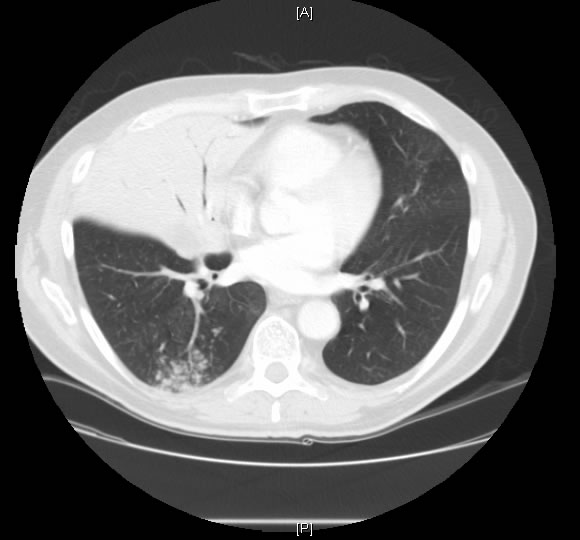

One month prior to presentation his SpO2 was 93% on room air. However, at the time of presentation his SpO2 was 80% and did not increase significantly with low flow oxygen. An arterial blood gas study performed on 100% oxygen yielded a PaO2 of 60 mm Hg, PaCO2 of 33 mm Hg, and pH of 7.33 [(A-a) pO2 gradient = 617 mm Hg] -- consistent with a right-to-left shunt of about 35%. Spirometry revealed FEV1 of 2.84L (77% of predicted), FVC of 3.87L (72% of predicted), and FEV1/FVC of 73%. His diffusion capacity was 24.9 (69% of predicted). During an oximetry walk test his SpO2 remained at 81%. An earlier incremental exercise test was terminated due to severe oxygen desaturation to 85%. Echocardiography revealed a left ventricular ejection fraction of 64%, but no evidence of intracardiac shunt. Quantitative ventilation and perfusion (V/Q) lung scan showed perfusion on the right side 42.3% and on the left side 57.7%, and ventilation on the right side 38.5%, and on the left side 61.5%, indicating some ventilation and perfusion defect.

At thoracotomy the right middle lobe was completely involved with and massively distended by tumor, and there was significant hilar and intraparenchymal adenopathy. Rather than a single middle lobe vein, there were three veins, each significantly hypertrophied, 4-8mm in size. A right middle lobectomy was performed. Ligation of the middle lobe veins resulted in immediate 100% saturation from 85%. A completion right pneumonectomy was performed because of positive margins. The patient was discharged on the third post operative day without supplemental oxygen and was able to maintain his saturation above 90% while breathing room air. Pathological examination of the tumor did not reveal an anatomic cause for the intratumor shunt. There was no evidence of vascular malformation, endobronchial obstruction, or invasion of major vessels. The background lung showed evidence of emphysema. The tumor was identified as a papillary adenocarcinoma.

This patient had an adenocarcinoma of his right lung and presented with severe refractory hypoxemia. Prior to surgery right-to-left intracardiac shunt was ruled out via echocardiography. In spite of an intrapulmonary shunt, the patient had good spirometric indices favorable for surgical resection. Preoperative suspicion that his refractory hypoxemia was due to a right-to-left intrapulmonary shunt was confirmed when saturation improved remarkably after ligation of the tumor. The tumor was identified as papillary adenocarcinoma, which shares many morphologic features with bronchioloalveolar carcinoma - growth along alveolar walls and tendency for aerogenous spread. Papillary lung carcinoma can show histopathologic features similar to those seen in the ovary or thyroid gland. Thus, a detailed clinical history is particularly advised. To the best of our knowledge, these types of tumors are no more prone to develop shunts, produce vasogenic substances or induce neoangiogenesis than other histologic types of lung adenocarcinomas. Chetty et. al3 reported a case of bronchioalveolar carcinoma in which the patient also had refractory hypoxemia that cleared upon ligation of the tumor. Pathologically, that tumor had an abundance of dilated vessels.3 We saw similar changes surgically, but not on pathological examination. An alternate explanation for our findings is that exceedingly high intralobar pressure, distal to the precapillary sphincter resulted in insufficient perfusion pressure to reach the alveoli, resulting in shunting through precapillary A-V communications and thus greater flow through the RML venous system. Previous literature on this topic made few references to intratumoral shunting. There often may be no clearly discernable anatomic/pathologic correlate for clinically obvious intrapulmonary shunting. A preoperative diagnosis may be demonstrated via V/Q scan, angiography, or pulmonary artery occlusion, but in this case the presumptive diagnosis was based on clinical suspicion and exclusion of intracardiac shunt by echocardiogram. Immediate resaturation upon removal of the tumor confirmed our suspicion that our patient was shunting through a tumor. The lesson learned from this case is that hypoxemia, instead of being a contraindication of surgery, may occasionally be correctable by surgery. Our patient easily could have been denied surgery on the basis of severe, refractory hypoxemia. Therefore pulmonary shunting through the tumor should be considered as a possible cause of refractory hypoxemia; appropriate studies should be performed to exclude this possibility before denying such patients surgery.